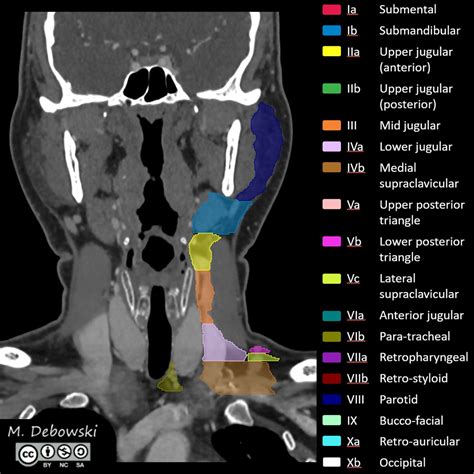

A CT scan of neck, often referred to as computed tomography, is a sophisticated diagnostic imaging procedure that utilizes X-rays combined with computer processing to create detailed, cross-sectional images of the structures within your neck. Whether your physician is investigating a persistent lump, evaluating unexplained pain, or monitoring a known condition, this imaging tool provides a level of clarity that standard X-rays cannot match. By capturing slices of the neck’s anatomy—including the thyroid gland, lymph nodes, blood vessels, and spinal structures—doctors can pinpoint abnormalities with remarkable precision, making it an essential component in modern diagnostic medicine.

Medical professionals order a CT scan of neck for a wide variety of reasons. Because the neck is a complex area housing vital pathways for breathing, swallowing, and blood flow to the brain, it is crucial to have accurate diagnostic data. This scan is frequently used to evaluate issues that require detailed visualization beyond what a physical examination can reveal.

• Tumor Staging: Assessing the size, location, and potential spread of cancers within the head and neck region.